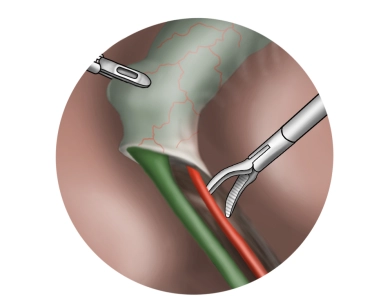

Transfemorale Katheter-Embolektomie nach Fogarty bei embolischem Verschluss der A. iliaca externa links